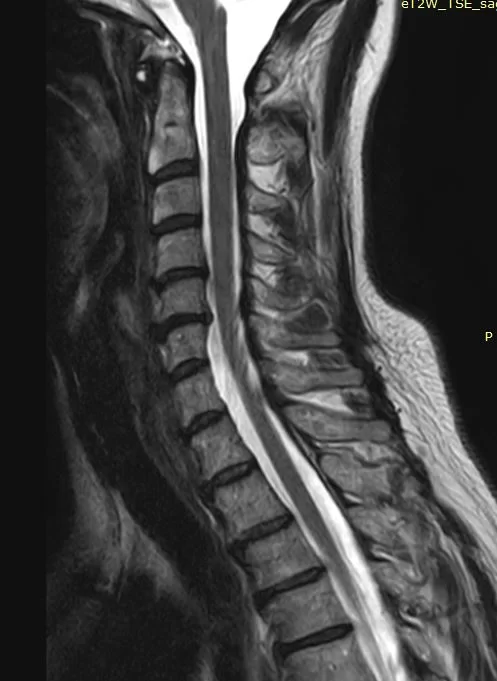

Ο απεικονιστικός έλεγχος με μαγνητική και αξονική τομογραφία της σπονδυλικής στήλης ανέδειξε εικόνα δισκοκήλης στα επίπεδα Α5/6 και λιγότερο Α4/5. Το σημαντικότερο εύρημα ήταν η πλάγια τρηματική στένωση με πίεση επί των ριζών Α6 & Α5 αριστερά.

Προεγχειρητική Μαγνητική Τομογραφία ΑΜΣΣ